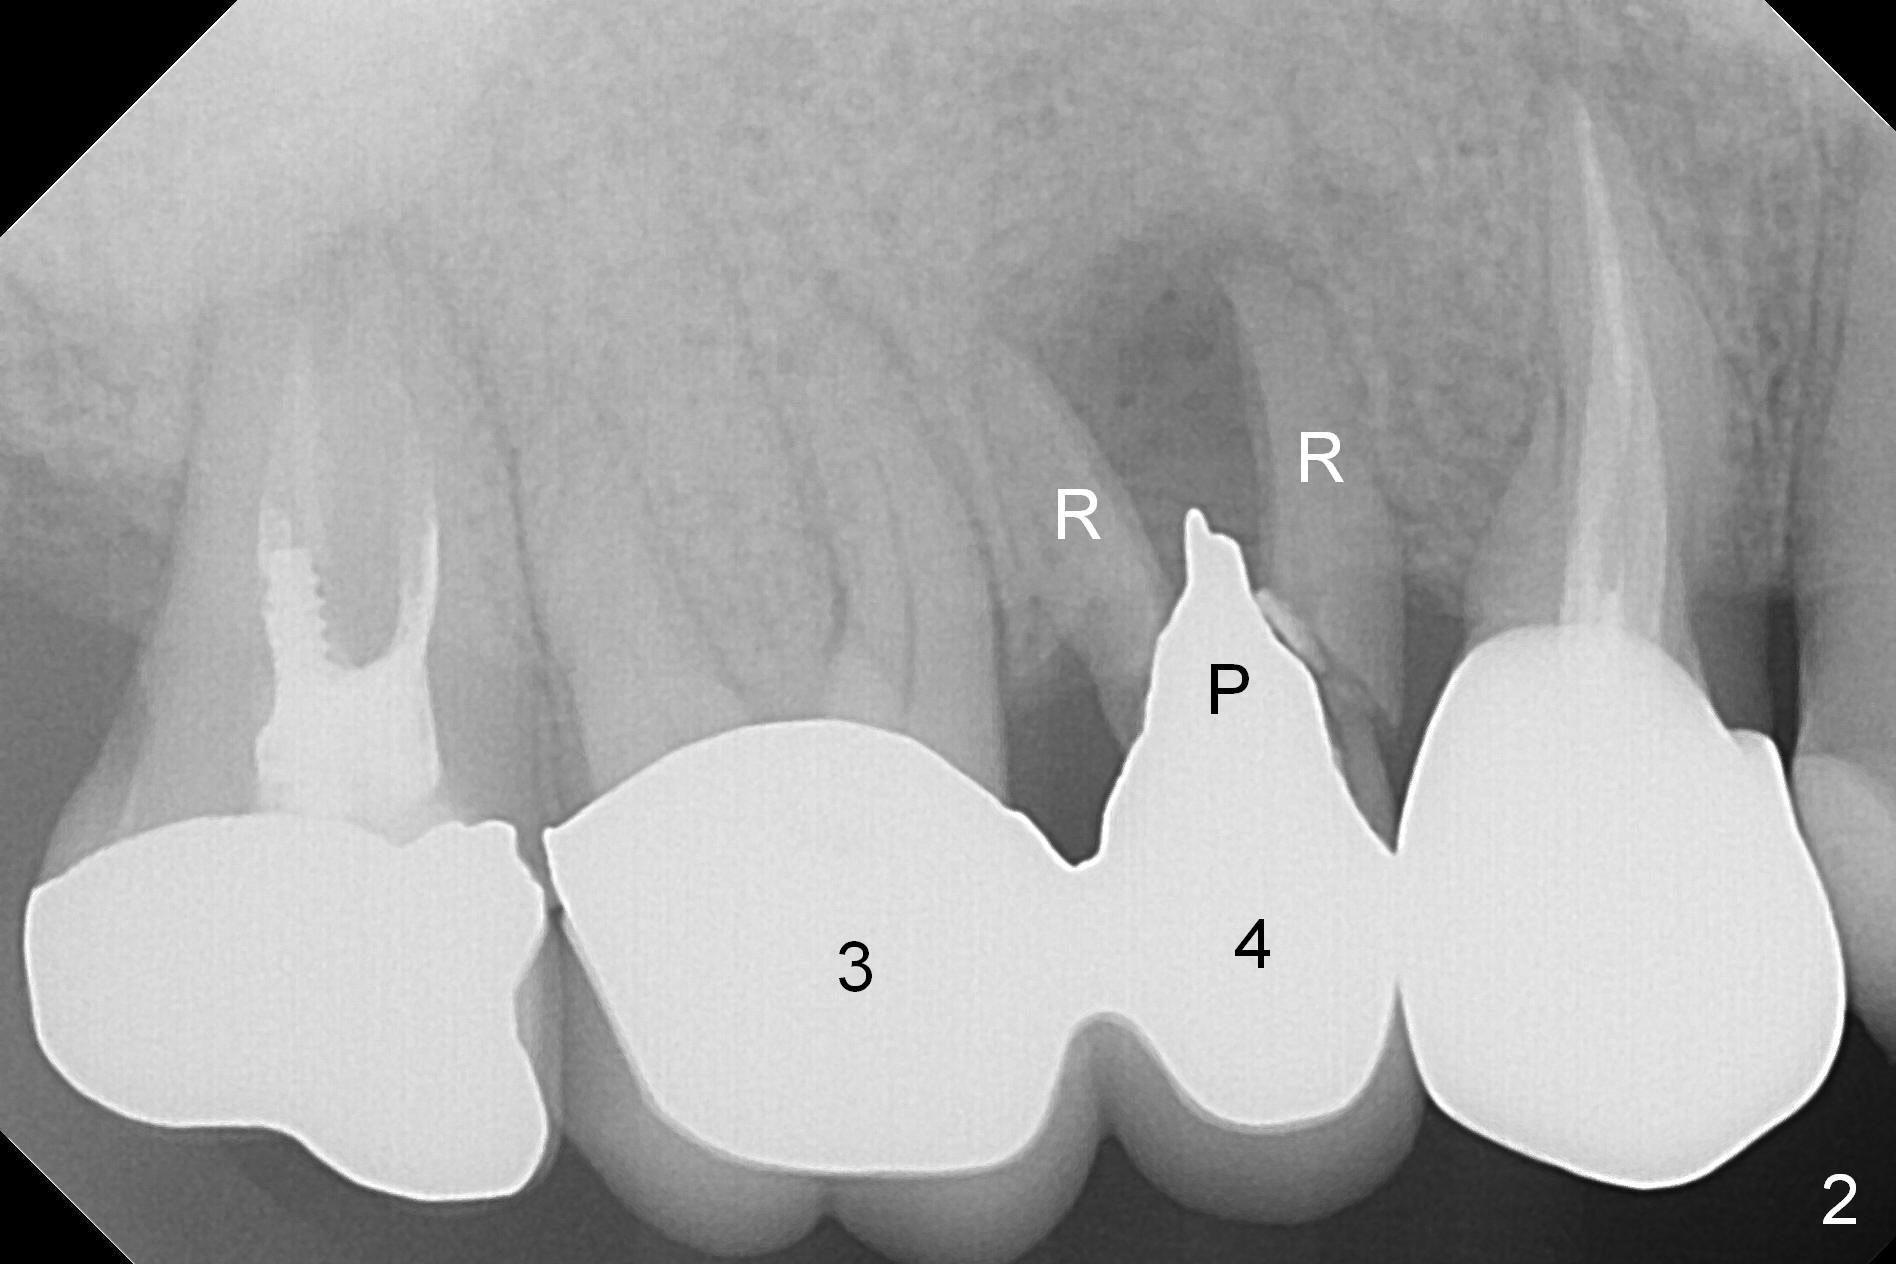

A 42-year-old man returns with chief complaint of chipped tooth at #3. Crowns at #3 and 4 are splinted (Fig.1). The tooth #4 is discolored (^). X-ray exam shows post (P) -induced Root (R) split with severe bone loss at #4 (Fig.2). To decrease periimplantitis, use an implant as narrow as possible (4 mm) and as long as apical bone allows (13 mm, IBS, Fig.3). Section the retainer at #3 and remove the tooth #4 (Metronidazole). Prepare PVS impression to record socket morphology. Magic Expanders are to be applied for osteotomy and sinus lift if possible. Finally fabricate splinted provisional at #3 and 4.